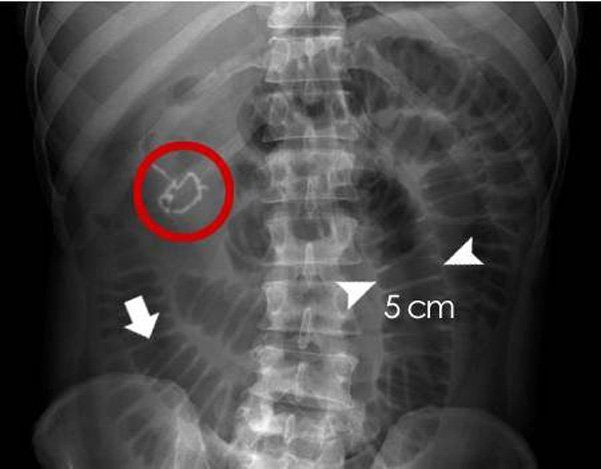

- X-quang tắc ruột: Chụp X-quang bụng có thể cho thấy dấu hiệu của khí bị mắc kẹt và nơi tắc nhưng X-quang tắc ruột không phải lúc nào cũng là phương pháp khả thi nhất để chẩn đoán tắc ruột.